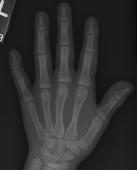

Bone Age Assessment is of great significance in determining the skeletal development age of children. It helps with the prediction of growth potential, the diagnosis of precocious puberty, and the identification of endocrine disorders [1]. Traditionally, radiologists assess bone age by observing the maturity of the phalanges, carpal, radius, and ulna based on left hand X-ray images and comparing them with established standards such as the Greulich–Pyle (GP) atlas [2] and the Tanner–Whitehouse (TW) scores [3, 4, 5]. The GP method is a template matching method, in which X-ray images are compared with annotated image sets and the matching results are used as the evaluation results. The GP method has been widely used internationally due to its simplicity, clarity, and ease of application. The TW method defines regions of interest (ROIs), the radiologist scores each ROI and then sums them up to determine the maturity of hand bone. However, both of these clinical methods rely heavily on the experience of radiologists, leading to marked inter-observer and intra-observer variability. Additionally, the ROIs annotation and bone age assessment are time-consuming and laborious. In recent years, with the remarkable progress in computational power and the development of deep learning techniques, many researchers have focused on developing rapid, accurate, and more objective BAA methods. Deep learning techniques have achieved remarkable success in various tasks within computer vision, medical image analysis, and biomedical fields. In the domain of BAA, the research methods mainly include traditional learning methods and deep learning methods.

In this article, we present an enhanced method named BoNet+. The architecture of this network is visually depicted in Fig.1. First, we cropped the whole hand radiographs based on the official bounding boxes and keypoints [11]. Then we resized the cropped regions to 500×500 pixels, generating both the cropped images and the attention maps, and applied data augmentation methods including brightness adjustment, contrast adjustment, random affine transformation, and horizontal flipping to the cropped images. The cropped images serve as the input to the Global Feature Extraction Channel, while the attention maps are fed into the Local Feature Extraction Channel. The Global Feature Extraction Channel captures global hand morphology features, whereas the Local Feature Extraction Channel focuses on local epiphyseal regional features. Both types of features are critical in the clinical BAA process. The global and local features are then concatenated along the channel dimension, thereby achieving comprehensive and efficient utilization of multilevel skeletal information. Subsequently, the fused features undergo further extraction and fusion by the Inception-V3 network. Finally, the predicted bone age is obtained through two fully connected layers and a linear layer. In the following parts of this section, we will offer a comprehensive and detailed exposition of each component of the network.

The proposed method was validated on two public datasets: the RSNA dataset [14] and the RHPE dataset [11]. Both datasets provide official splits that have been widely adopted to ensure comparability across different methods, and all comparative methods in this paper use the same splits. The RSNA dataset, sourced from the 2017 RSNA Pediatric Bone Age Challenge, includes 14,236 X-ray images, with bone ages ranging from 0 to 228 months (0 to 19 years). The dataset is divided into a training set (12,611 images), a validation set (1,425 images), and a test set (200 images). The RHPE dataset includes 6,288 X-ray images, with bone ages ranging from 0 to 240 months (0 to 20 years). It is divided into a training set (5,492 images), a validation set (716 images), and a test set (80 images). The distribution of the size of samples across different age groups in these datasets are shown in Fig.2. It is noted that female patients account for 46% and male patients account for 54%. Besides, on the RSNA dataset, the age groups of 1-7 , 8-15 , and 16-20 account for 23.4%, 72.4%, and 4.2% respectively. On the RHPE dataset, the corresponding age groups account for 24.3%, 70.7%, and 5.0%. The uneven distribution of samples across age groups, particularly the limited size of samples in certain age groups, poses a considerable challenge for bone age assessment.